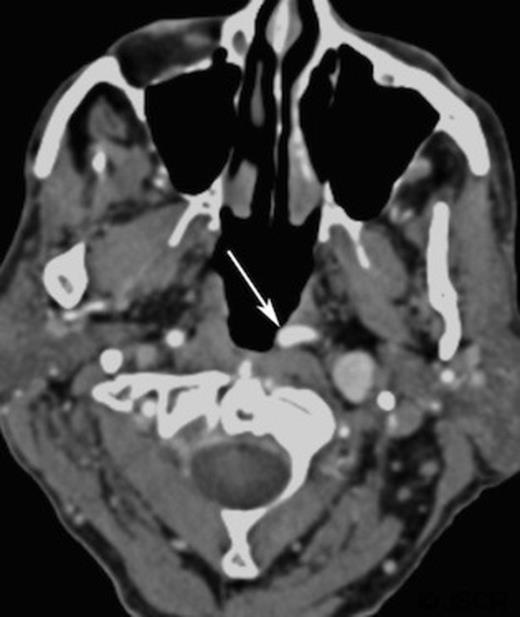

A CT scan, requested as part of his lymphoma follow-up, revealed asymmetrical fullness of the left nasopharynx due to a mass in the retropharyngeal space.(Figure 1) Owning to patient intolerance, nasoendoscopy was difficult in the clinic setting, and the nature of this swelling could not be properly determined. With the history of previous malignant disease, and the risk of recurrence or new disease being high, a biopsy was requested by the oncology team. However, since the CT imaging showed that the bulging mass could possibly be an artefact of a medially coursing left internal carotid artery (ICA), it was decided to perform a magnetic resonance imaging (MRI) prior to the biopsy. The MRI confirmed the ICA ectasia (often referred to as tonsillar loop) which manifested the asymmetry of the contour of the nasopharynx with prominence and fullness on the left just below the fossa of Rosenmuller.(Figure 2) There was no evidence of any mucosal abnormalities of nasopharynx or of the remainder of upper aerodigestive tract. No other pathological lesion was noted and the biopsy was cancelled.

Short inversion time inversion recovery (STRI) axial magnetic resonance imaging of the retropharyngeal region (arrow)